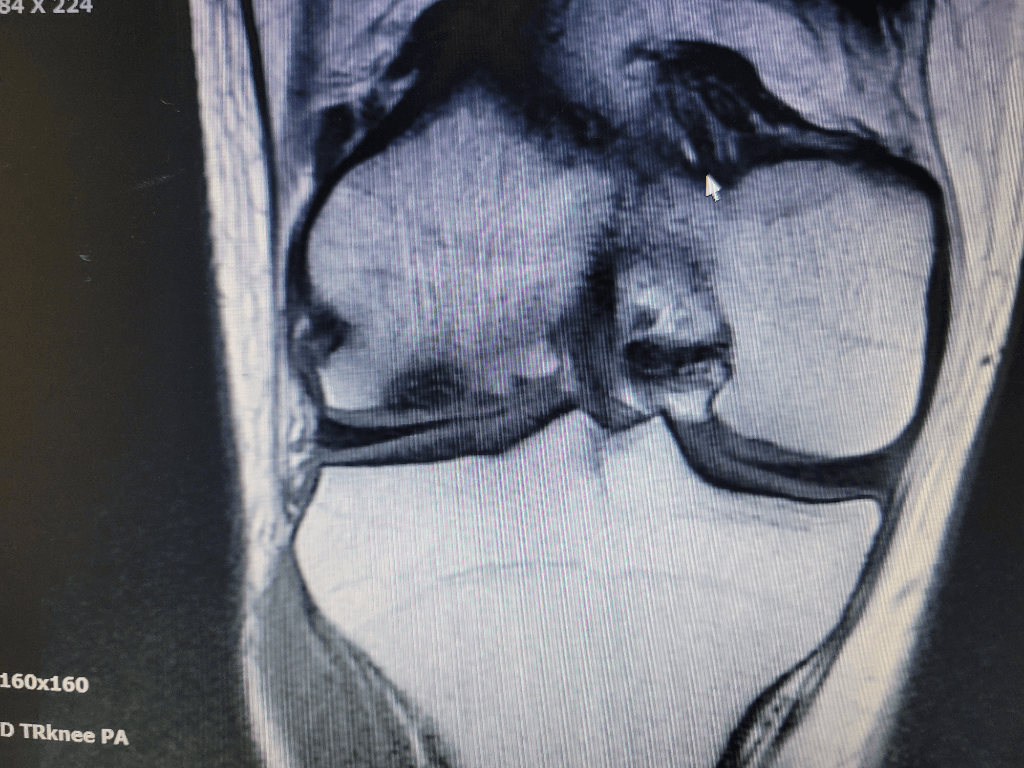

작년 9월에 찍은 무릎 mri를 보는데 검정색으로 된 부위가 있어서 걱정돼서 여쭤봅니다.

과거 박리성 골연골염 수술을 받은적이 있고 약 1년 전부터 통증이 다시 발생하여 재발하거나 괴사했을까봐 걱정이 많이 됩니다. mri 판독 한번만 부탁드립니다.

• 안녕하세요. 유민혁 의사입니다.

MRI는 보통 500-1000장 정도의 사진으로 이루어져 있습니다.

올려주신 사진은 그 중 2장이기 때문에 판독할 수 없습니다.